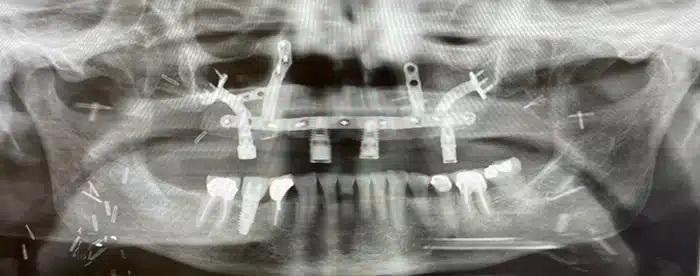

The next step would focus on the reconstruction and rebuilding of her upper jaw using a free tissue transfer, or free flap. The procedure involved the transplant of the fibula bone, skin, and blood vessels from the lower leg to reconstruct the upper jaw and palate. Specialized hardware was also designed to hold the transferred tissue in place, plus dental implants for adding a prosthesis for the replacement of Sue’s teeth.

With the assistance of Nagi Demian, DDS, MD, professor and Thomas M. Weil Professorship in Oral and Maxillofacial Surgery at UTHealth Houston School of Dentistry, intraoperative navigation techniques were utilized to ensure the reconstruction went exactly as planned, allowing for the placement of the dental implants created for Sue’s new teeth.